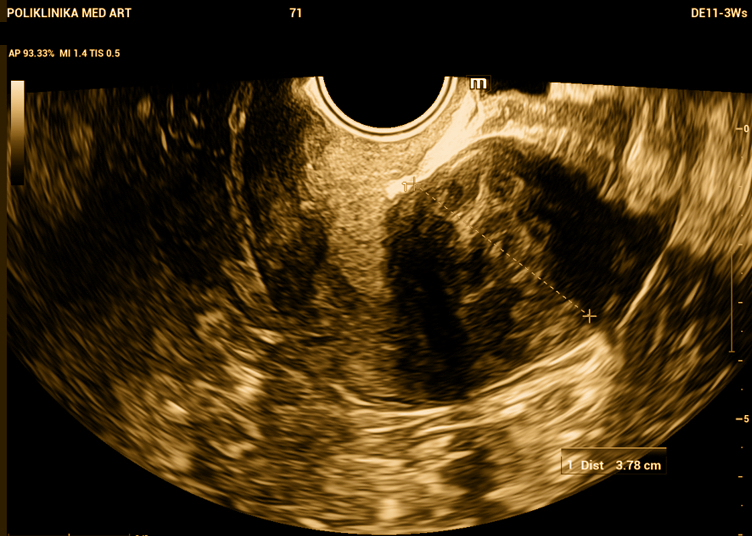

Jedan veći subserozni miom. Svojim volumenom izlazi iz tijela maternice.

Ako nastavi s rastom, može pritiskati okolne strukture – mokraćni mjehur, crijeva ili uretere, ovisno o položaju.

Miom promjera 37 mm, kao ovaj, ne bi trebao raditi većih tegoba.